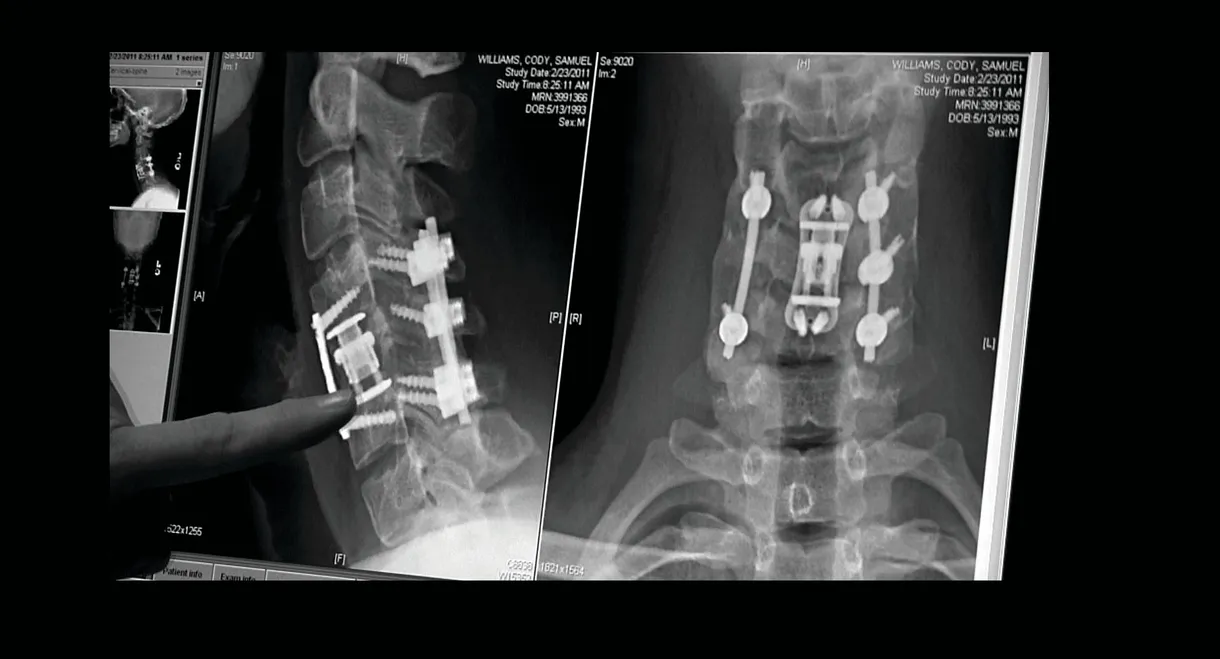

The compelling, heart-wrenching story of high school football star Chris Carnales, whose life changed when he became paralyzed after breaking his neck in a football game. Chris soon learned of others who suffered similar injuries and, with the help of his father, overcame tremendous pain to start an organization with one goal in mind: get immediate help to other victims and their families. He called it Gridiron Heroes.